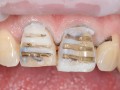

Technika Injection Flowable i technika stempla. Odbudowa…

Aneta Neskoromna, Aneta Mamos, Dawid Zagaki